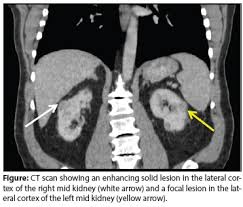

Renal Cancer Management In A Patient With Chronic Kidney Disease